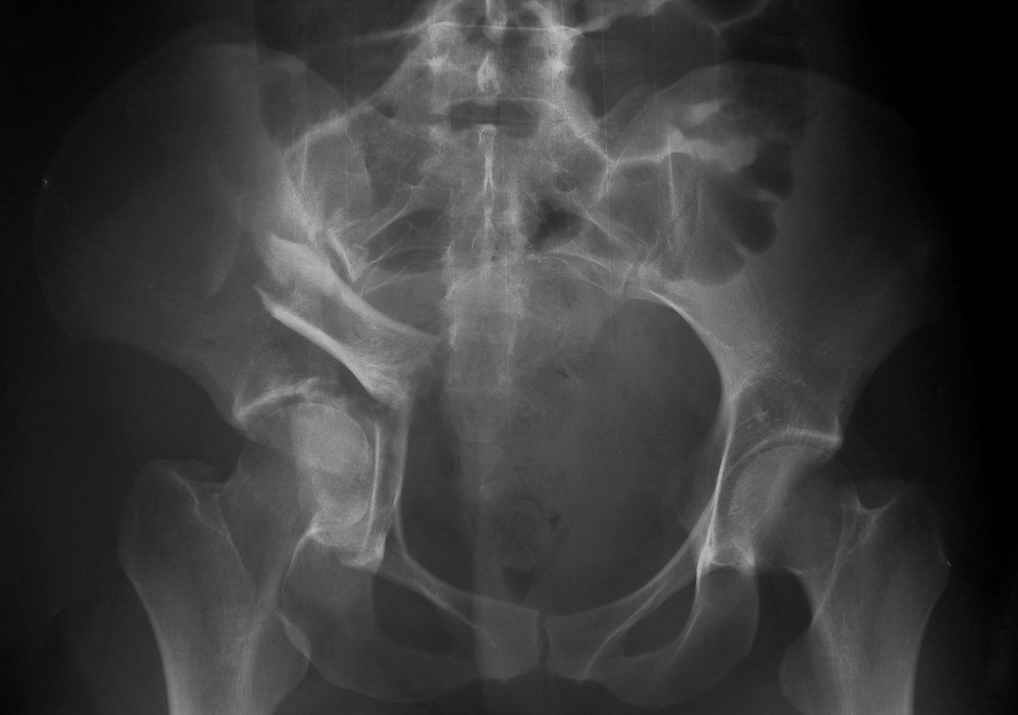

Вот еще одно наблюдение не совсем частое, большое желание поставить распорку поперек таза, чтобы вернуть конфигурацию тазового кольца.

Но считаю, что третий сорт не брак, тем более-то ноги одинаковые. Доступ между подвзлошно-паховым и подвздошно-бедренным, пришлось несколько расширяться книзу, но внимательно не посмотрел и попал на бедро, надо было все-таки по паховой складке, но вот беда - на хорошо загорелом теле не нашел следов более светлой кожи, поэтому рубец будет несколько выступать из под бикини. Посылаю три снимка. Пока. Вернусь через 10 дней. Жду ответа. ЛАФ.